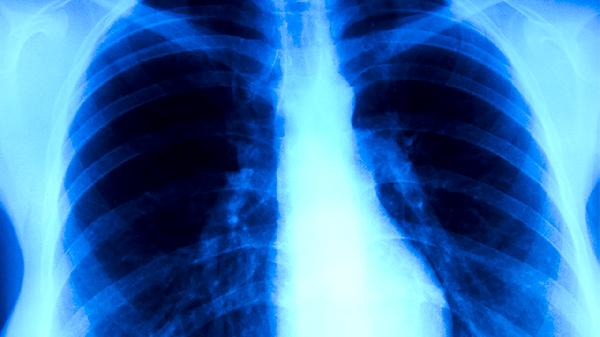

肺結(jié)核引起的并發(fā)癥是什么

肺結(jié)核可能引起肺源性心臟病、結(jié)核性腦膜炎、腸結(jié)核、骨關(guān)節(jié)結(jié)核、腎結(jié)核等并發(fā)癥。肺結(jié)核是由結(jié)核分枝桿菌感染引起的慢性傳染病,若未及時(shí)規(guī)范治療,病原體可能通過(guò)血液或淋巴系統(tǒng)擴(kuò)散至其他器官。

肺結(jié)核患者應(yīng)保證高蛋白飲食如雞蛋、魚(yú)肉,每日補(bǔ)充新鮮蔬菜水果。注意隔離痰液消毒,居住環(huán)境保持通風(fēng)干燥。嚴(yán)格遵醫(yī)囑完成6-8個(gè)月規(guī)范治療,定期復(fù)查胸部CT和痰菌檢測(cè)。出現(xiàn)新發(fā)癥狀如頭痛、血尿等需立即就醫(yī)排查并發(fā)癥。